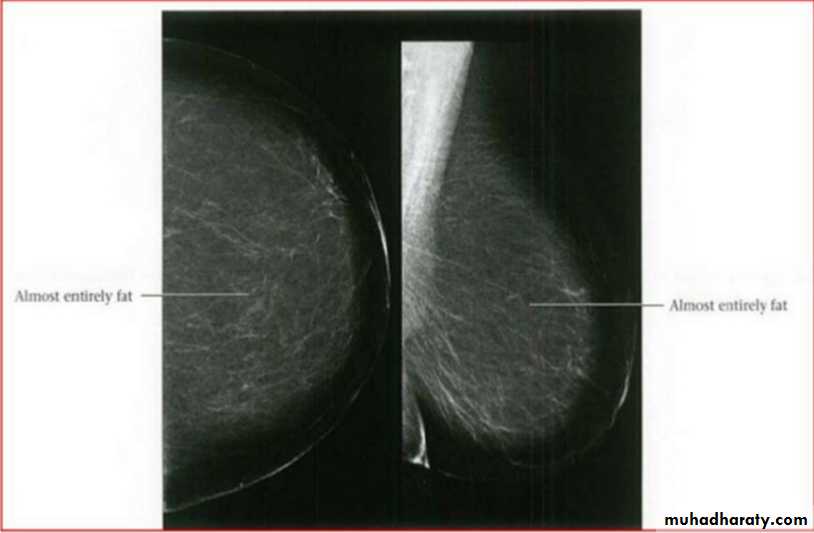

Breast density & who can U detect a mass lesion

Your mammogram report must take in consideration & assessment the breast density. Breast density is based on how fibrous and glandular tissue tissues are distributed in your breast, vs. how much of your breast is made up fatty tissue.

Dense breasts are not abnormal, but they are linked to a higher risk of breast cancer. We know that dense breast tissue can make it harder to find cancers on a mammogram. Still experts do not agree what other tests, if any, should be done in addition to mammograms in women with dense breasts who aren’t in a high-risk group (based on gene mutations, breast cancer in the family, or other factors